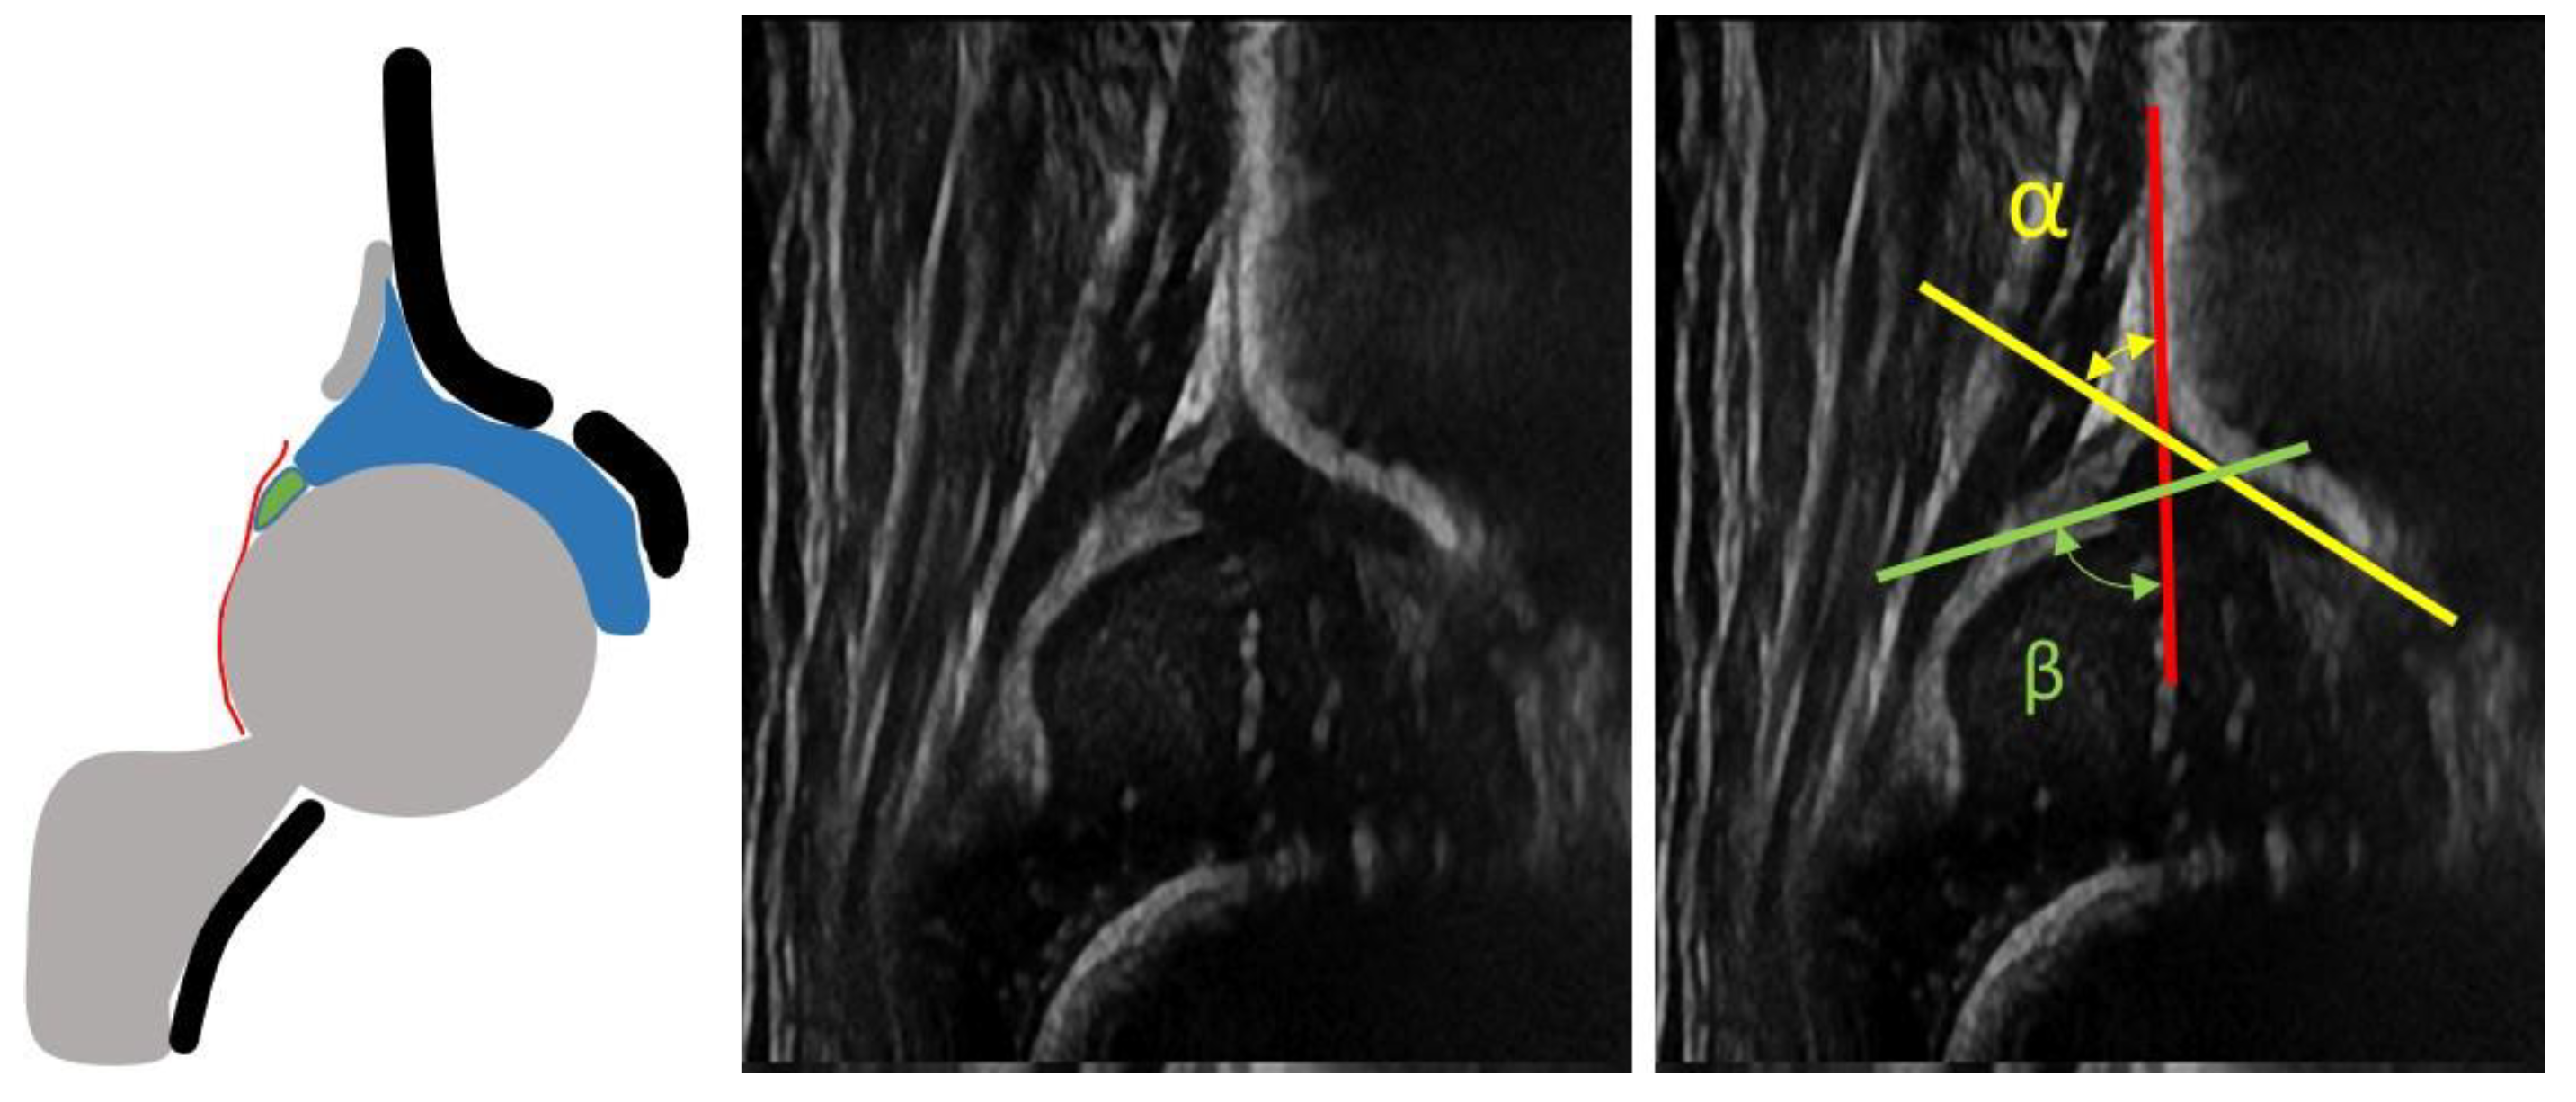

- infants with type I hips at the US examination according to Graf classification (Figure 1)